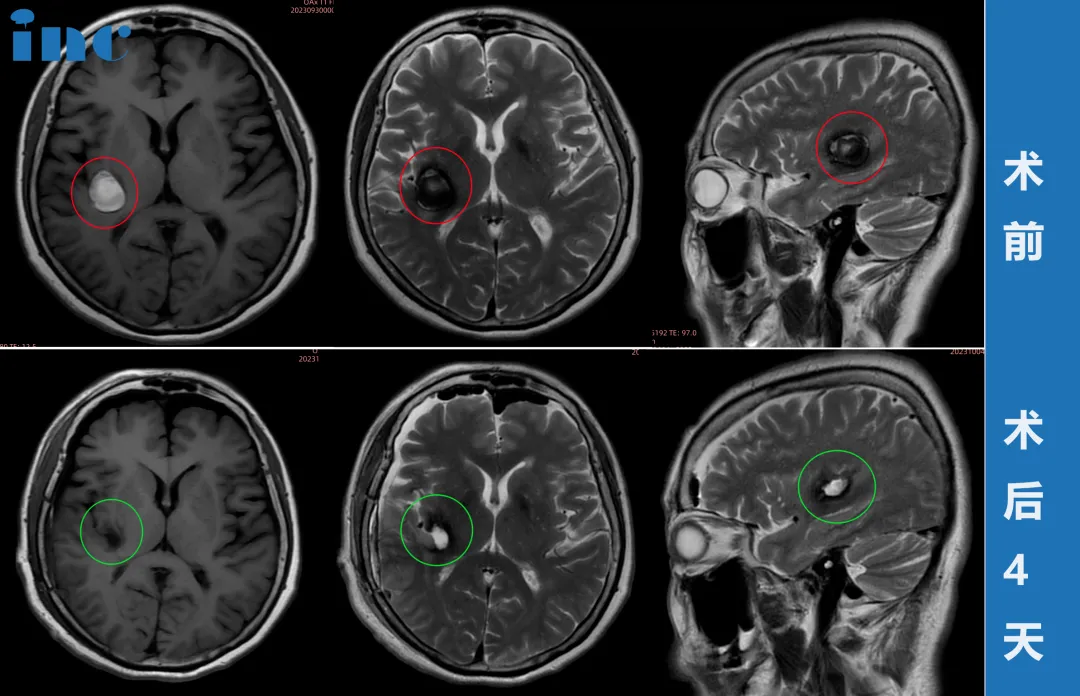

柯阿姨紧急做了新的MRI,结果显示:病灶又增大了!当巴教授查看最新核磁图像后,告知患者随时会有出血风险,需要立即手术。

9月29日,柯女士和家人与巴教授紧急视频沟通之后,决定提前手术。

10月1日,在苏州大学附属第四医院,巴教授顺利完成手术,无任何新发神经功能损伤。

术后第2天巴教授查房时,柯女士精神状态非常好,已经可以下地走路。柯女士一家人终于松了一口气,这个困扰他们已久的问题终于得到完美的解决。